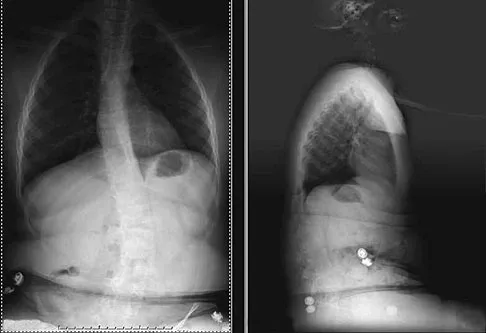

Figure 24 shows the sitting AP and lateral spinal radiographs of a nonambulatory 12½-year-old boy with Duchenne muscular dystrophy who is being evaluated for scoliosis. The lumbar curve from T12 to L5 measures 36 degrees, and the thoracic curve from T3 to T12 measures 24 degrees on the AP radiograph. He has 5 degrees of pelvic obliquity. His forced vital capacity is 45% of predicted for height and weight. What is the most appropriate treatment for the spinal deformity?